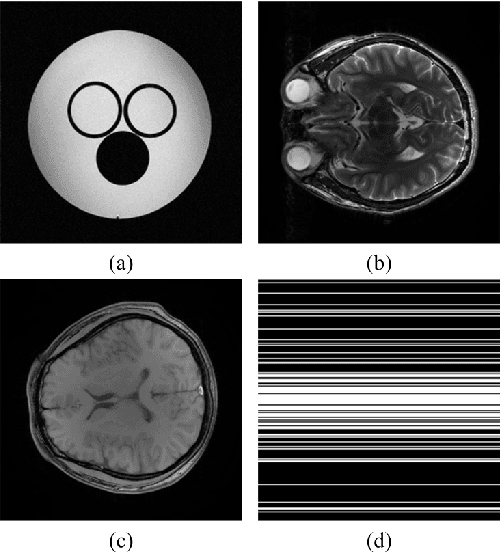

Compressed sensing has shown great potentials in accelerating magnetic resonance imaging. Fast image reconstruction and high image quality are two main issues faced by this new technology. It has been shown that, redundant image representations, e.g. tight frames, can significantly improve the image quality. But how to efficiently solve the reconstruction problem with these redundant representation systems is still challenging. This paper attempts to address the problem of applying iterative soft-thresholding algorithm (ISTA) to tight frames based magnetic resonance image reconstruction. By introducing the canonical dual frame to construct the orthogonal projection operator on the range of the analysis sparsity operator, we propose a projected iterative soft-thresholding algorithm (pISTA) and further accelerate it by incorporating the strategy proposed by Beck and Teboulle in 2009. We theoretically prove that pISTA converges to the minimum of a function with a balanced tight frame sparsity. Experimental results demonstrate that the proposed algorithm achieves better reconstruction than the widely used synthesis sparse model and the accelerated pISTA converges faster or comparable to the state-of-art smoothing FISTA. One major advantage of pISTA is that only one extra parameter, the step size, is introduced and the numerical solution is stable to it in terms of image reconstruction errors, thus allowing easily setting in many fast magnetic resonance imaging applications.